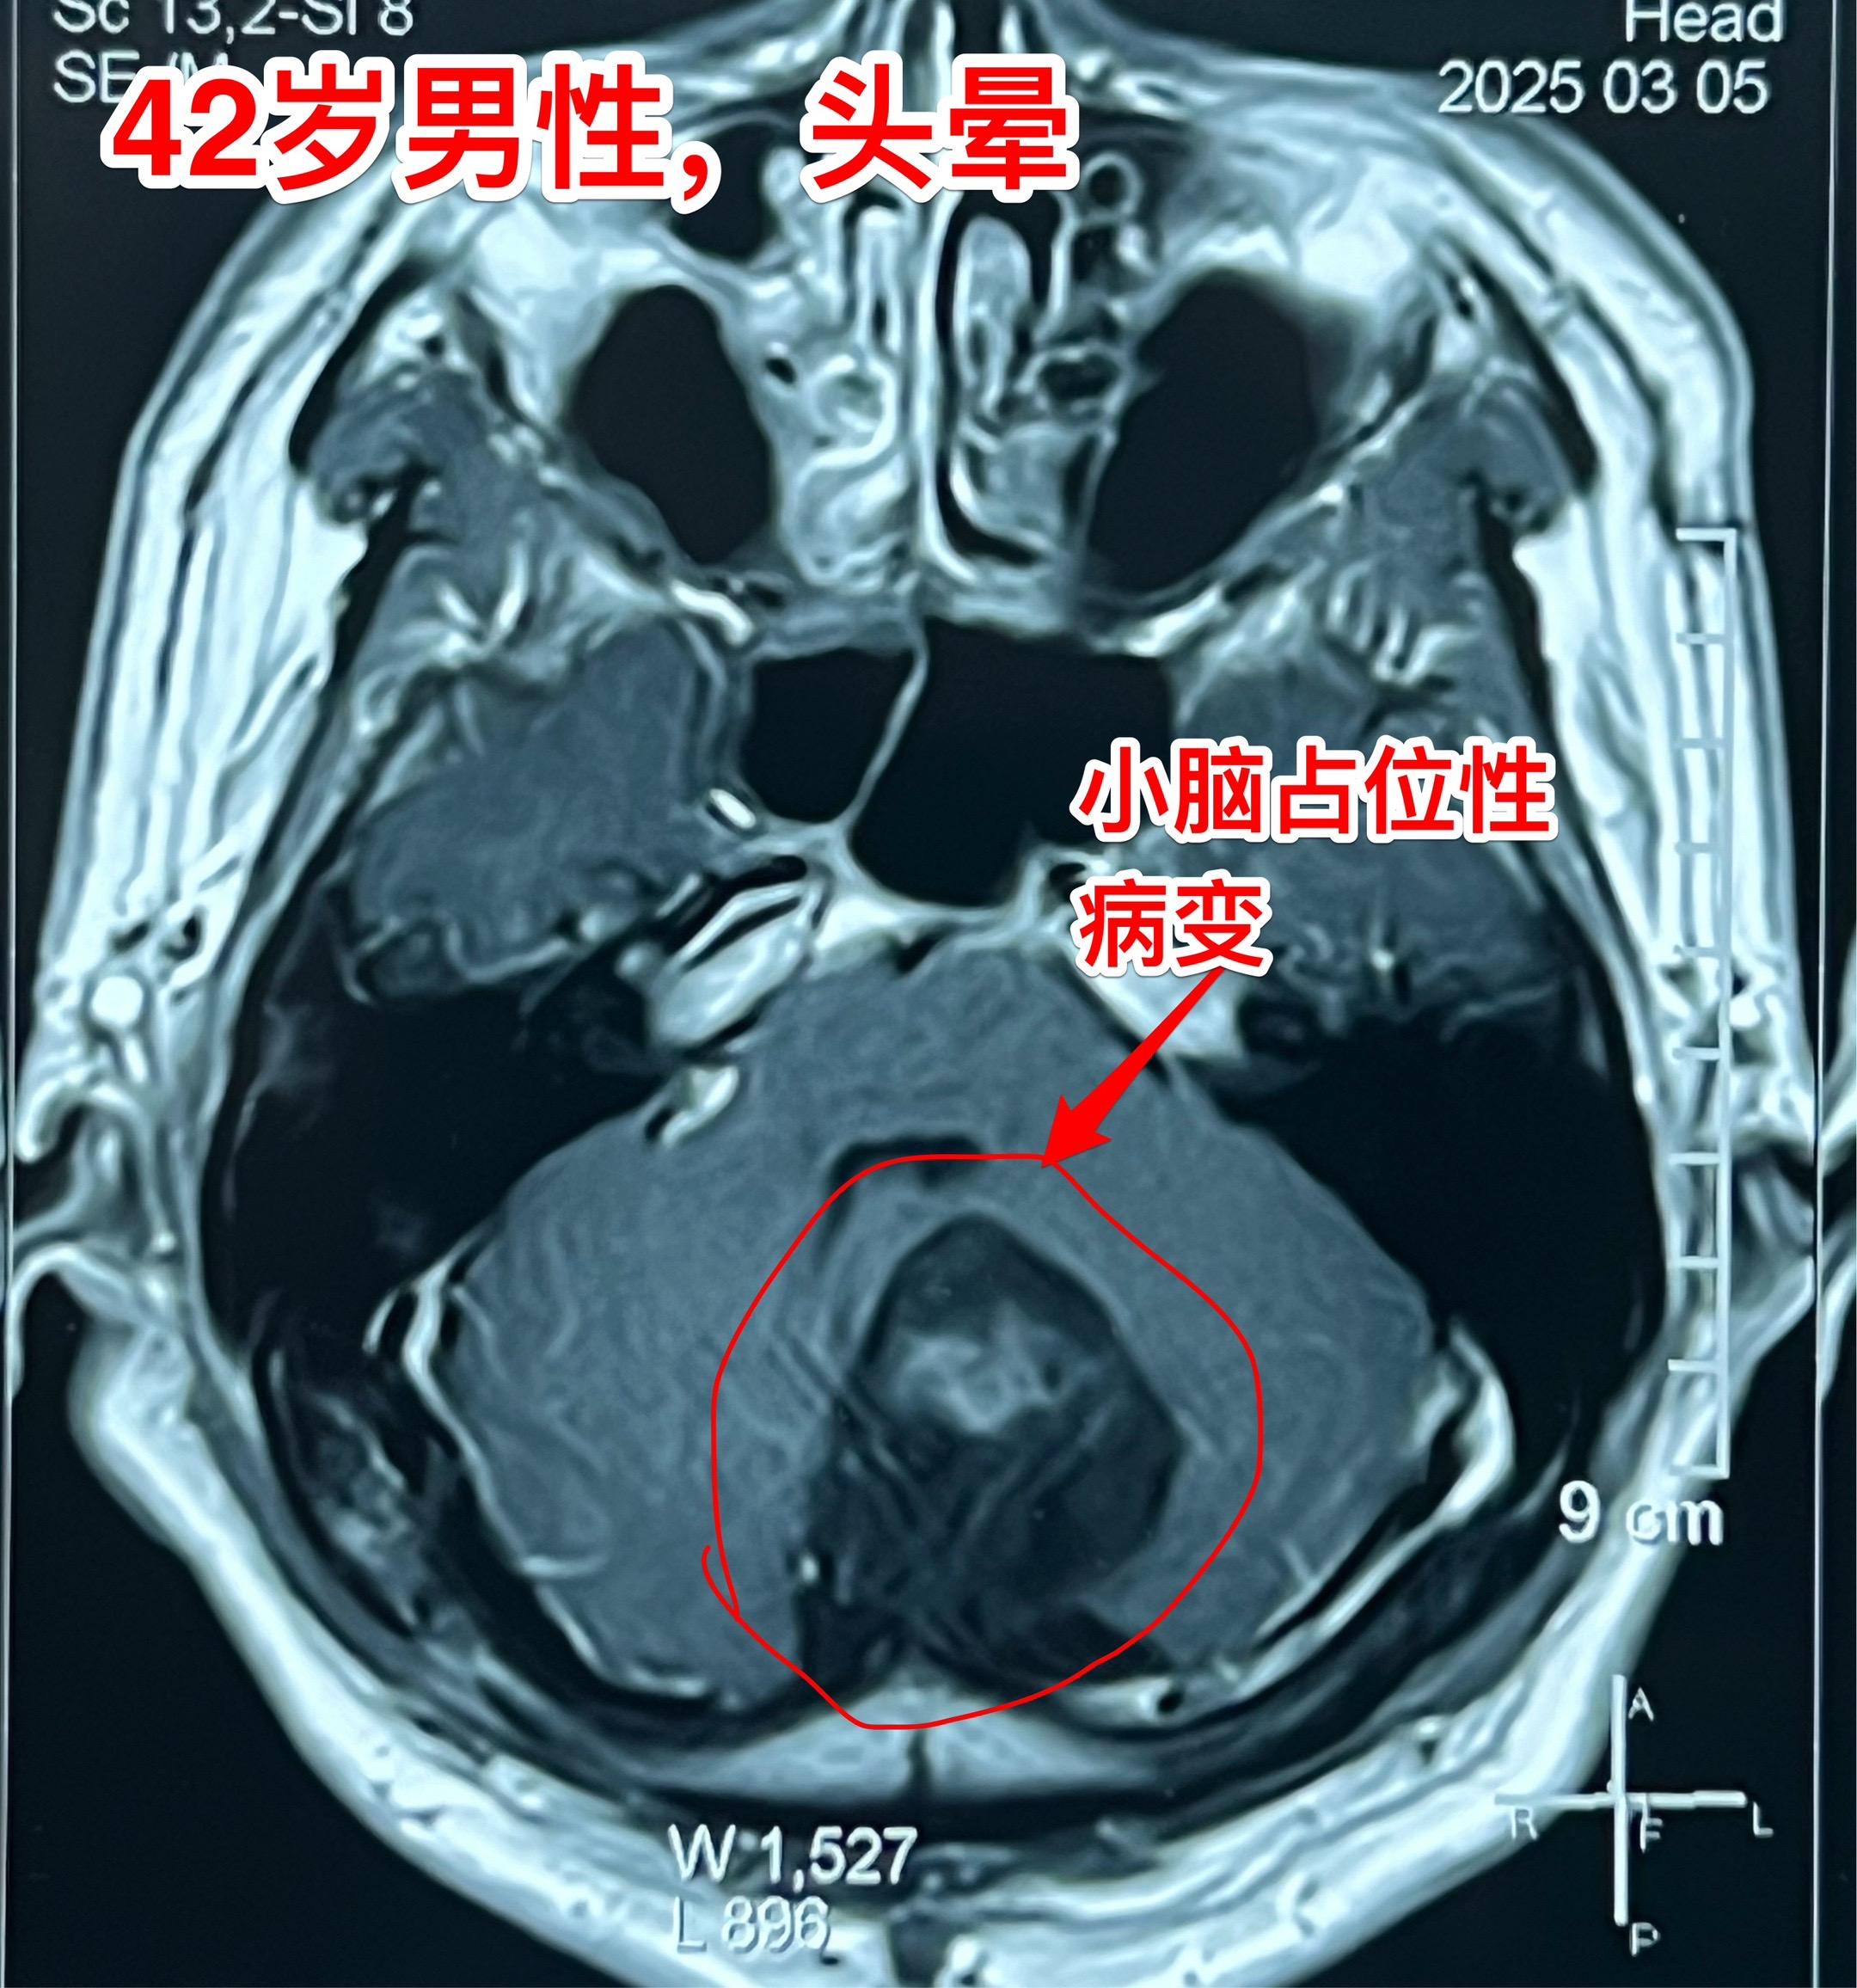

表皮样囊肿(胆脂瘤)并不是真正的肿瘤。这是先天性胚胎发育异常造成的疾病,脑部发育过程中神经管闭合时,一小部分外胚层细胞被关在脑子里面了。本来要发育成皮肤的细胞留在脑子里面,逐步增大,就形成了表皮样囊肿,也叫珍珠瘤,或者胆脂瘤。它不是真正的肿瘤,是表皮细胞脱落逐步增大形成了一个占位性病变。这个病也有恶变的,几率很小。 这个42岁的内蒙古男性,因头晕怀疑颈椎病,在锡林浩特作磁共振检查发现了小脑表面有个占位性病变,见图。DWI显示病灶是白色的,可以确诊为表皮样囊肿。 昨日作了手术